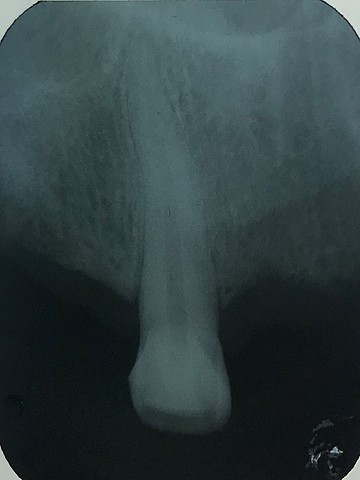

• Serie Radiográfica

Serie Radiográfica

Se realizó una serie radiográfica de todos los órganos dentales, en el cual se observo una lesión apical en el órgano 1.7. se le dio una orden para la radiografía panorámica.